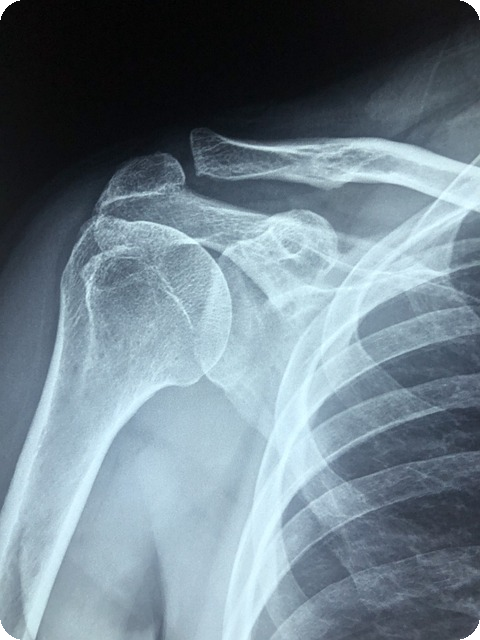

전문가의 도움 받기

관절 통증이 심해지거나 일상생활에 지장을 준다면, 주저하지 말고 전문가의 도움을 받는 것이 중요합니다. 정확한 진단을 통해 통증의 원인을 파악하고, 적절한 치료 및 관리 방법을 모색할 수 있습니다. 정형외과에서는 물리치료, 주사 치료, 그리고 약물 치료 등 다양한 방법으로 관절 기능을 회복할 수 있는 기회를 제공합니다.